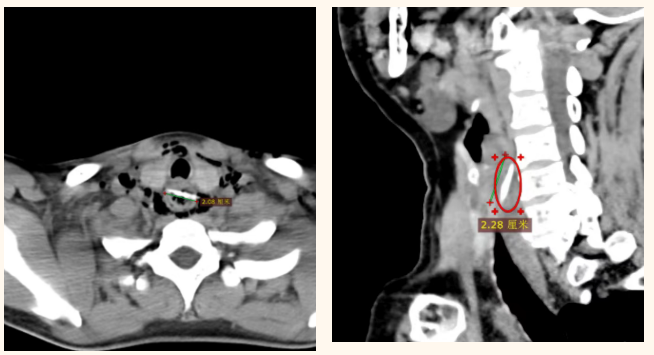

异物卡喉非小事,拖延治疗可能致命 在近期接诊的患者中,以误吞鸡骨头、鱼刺者居多。更令人揪心的是,近半数患者因疏忽早期症状,拖延多日才前来就诊,此时异物已对食管造成不同程度的损伤。有的患者出现颈部肿胀、皮下气肿,有的已形成纵隔脓肿、脓毒血症,更有甚者,鱼刺直接刺穿食管、扎破主动脉,随时可能引发致命性大出血,危及生命。 面对此类复杂危重病情,我院立即启动急诊救治绿色通道,胸甲状腺乳腺血管外科、消化内科、耳鼻喉科、麻醉科等多学科团队快速联动、高效协作:通过胸部CT精准定位异物的位置与形态,为治疗方案制定提供科学依据;消化内科与耳鼻喉科医生优先采用胃镜或硬质食管镜,尝试微创取出异物,最大限度减少患者创伤;对于内镜下难以取出的危重病例,胸甲状腺乳腺血管外科团队即刻完善手术方案,做好急诊手术准备。 其中,那例鱼刺刺穿主动脉的高风险患者救治尤为惊险。多学科团队紧急会诊后,先通过血管造影植入支架,成功封堵破损血管、筑牢安全防线,再精准操作取出异物,全程化险为夷,最终让患者顺利康复。截至目前,所有接诊的食管异物患者均已痊愈出院。 这些“土方法”千万别用,等于拿生命冒险 生活中,很多人遇到异物卡喉时,第一反应便是吞饭团、喝醋、抠喉咙,殊不知这些做法不仅无效,反而会对食管造成二次伤害,甚至危及生命。 ×吞饭团/馒头:会将卡在食管入口的异物强行推向深处,极易刺破薄弱的食管壁,原本可通过微创轻松取出的异物,可能因此需要开胸手术,加重患者痛苦与治疗风险。 ×喝醋:醋在食管内停留时间仅数秒,根本无法软化鱼刺、骨头等坚硬异物,反而会刺激已受损的食管黏膜,加重炎症反应,得不偿失。 ×强行催吐:剧烈呕吐会引发食管痉挛,可能导致异物刺入更深部位,甚至造成食管穿孔,引发严重感染。 ☑正确做法:立即停止进食、饮水,减少吞咽动作,保持情绪平稳,第一时间前往正规医院就诊。就诊时,尽量清晰告知医生误吞的异物类型、时间及自身症状,配合完成影像学检查,由专业医生判断最优治疗方案。需特别提醒的是,异物嵌顿24小时内是救治黄金期,此时内镜取出成功率高,并发症风险也最低,切勿拖延。 守护食管健康,记住这三个预防要点 我院胸甲状腺乳腺血管外科主任于福田提醒广大市民:食管异物看似是意外,实则大多可通过养成良好的进食习惯有效避免,牢记以下几点,守护自己和家人的食管健康。 ☑ 进食专注,细嚼慢咽:吃饭时避免说笑、看手机,集中注意力进食,每口食物咀嚼20次以上,尤其食用鱼类、带骨肉类时,务必仔细剔除骨头,切勿急躁。 ☑ 高危人群重点防护:老年人佩戴的假牙需定期检查松紧度,防止进食时脱落误吞;进食时尽量将食物切成小块,便于吞咽。儿童身边切勿放置硬币、纽扣电池等细小物件,避免在哭闹、跑动时喂食,防止误吞。 ☑ 摒弃危险操作:一旦误吞异物,切勿心存侥幸等待“自然排出”,更不要盲目尝试各类民间偏方,及时前往正规医院就诊,才是最安全、最可靠的选择。 美味诚可贵,安全价更高。愿每一位市民都能养成良好的进食习惯,警惕餐桌异物风险,我院多学科团队也将始终坚守岗位,以精湛医术、高效协作,为广大市民的生命健康保驾护航。